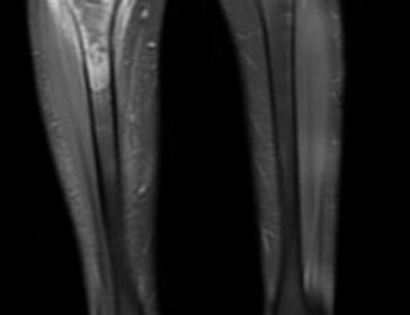

This is an MRI of the patient with a tumor located in their right tibia (upper left side of the image).